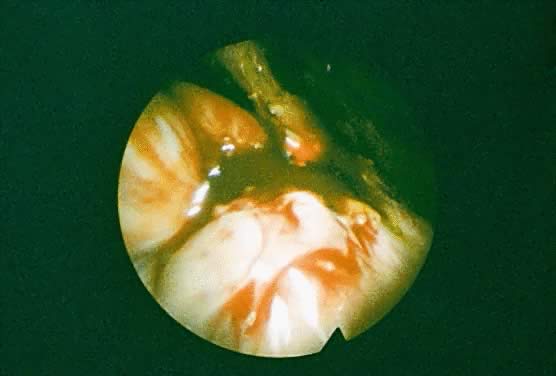

Endometriotic cysts typically are encountered in the ovary. Superficial ovarian implants are usually found on the lateral and inferior surfaces of the ovary and occur as irregular, variously pigmented lesions. After a cyst forms, cyclic hemorrhage within the cyst adds to the contents, causing cyst growth because of the slow reabsorption of debris. These endometriomas have been described as chocolate cysts because of the thick, tarry, dark brown fluid composed of blood and blood pigment that fills these cysts (Fig. 3). As intracystic pressure increases, the tendency for endometriomas is to perforate. This permits leakage of the highly irritating cyst contents that precipitates dense adhesion formation to adjacent organs. The site of perforation is typically involved in the adhesive process, rendering surgical removal of the cyst more difficult.

Fig. 3. Densely adherent ovary with an endometrioma containing “chocolate” fluid.